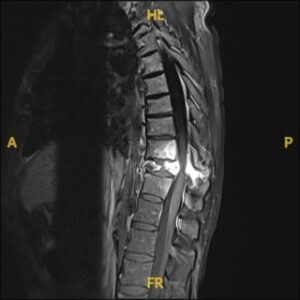

1. Pre-Surgical Evaluation: Includes imaging studies (MRI, CT, or X-rays), biopsy (if needed), and a thorough assessment of overall health.